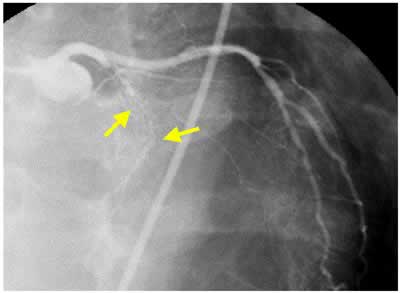

| Final CAG Findings:'01.9.5 LVG: asynergy (A), EF: 71% CAG: #6 90% (ISR) #7 CTO (collateral from RCA) |

I-3 : months follow-up angio